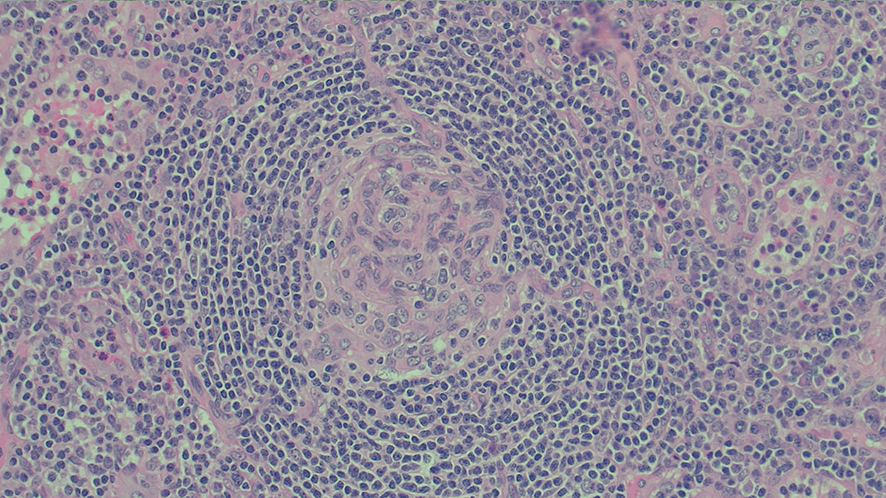

A positron emission tomography scan showed innumerable mildly to moderately fludeoxyglucose (FDG)‐avid enlarged and non‐enlarged lymph nodes above and below the diaphragm, and increased splenic and bone marrow activity (Box 3). Biopsy samples were taken from the most FDG‐avid axillary and mediastinal lymph nodes, but were non‐diagnostic. The results from one biopsy showed non‐caseating granulomas; however, results from the second biopsy did not. An excisional lymph node biopsy was subsequently taken, with the results meeting histopathologic criteria for Castleman disease (Box 4). These criteria included depleted germinal centres, concentric rimming of small B lymphocytes in a “onion skin” appearance, and vascularity with vessels extending into the germinal centre.1

Core lymph node biopsy results revealed non‐caseating granulomas, initially suspicious of sarcoidosis. However, non‐caseating granulomas may also indicate many viral, bacterial or fungal infections, vasculitides, occupational diseases and haematological disorders.2 Core lymph node biopsies can provide definitive diagnosis in more than 92% of cases. However, they have an increased rate of incorrect and non‐conclusive diagnosis compared to an excisional lymph node biopsy.3 Excisional lymph node biopsies should be pursued if any diagnostic ambiguity exists. In this case, excisional lymph node biopsy results led to our diagnosis of Castleman disease.